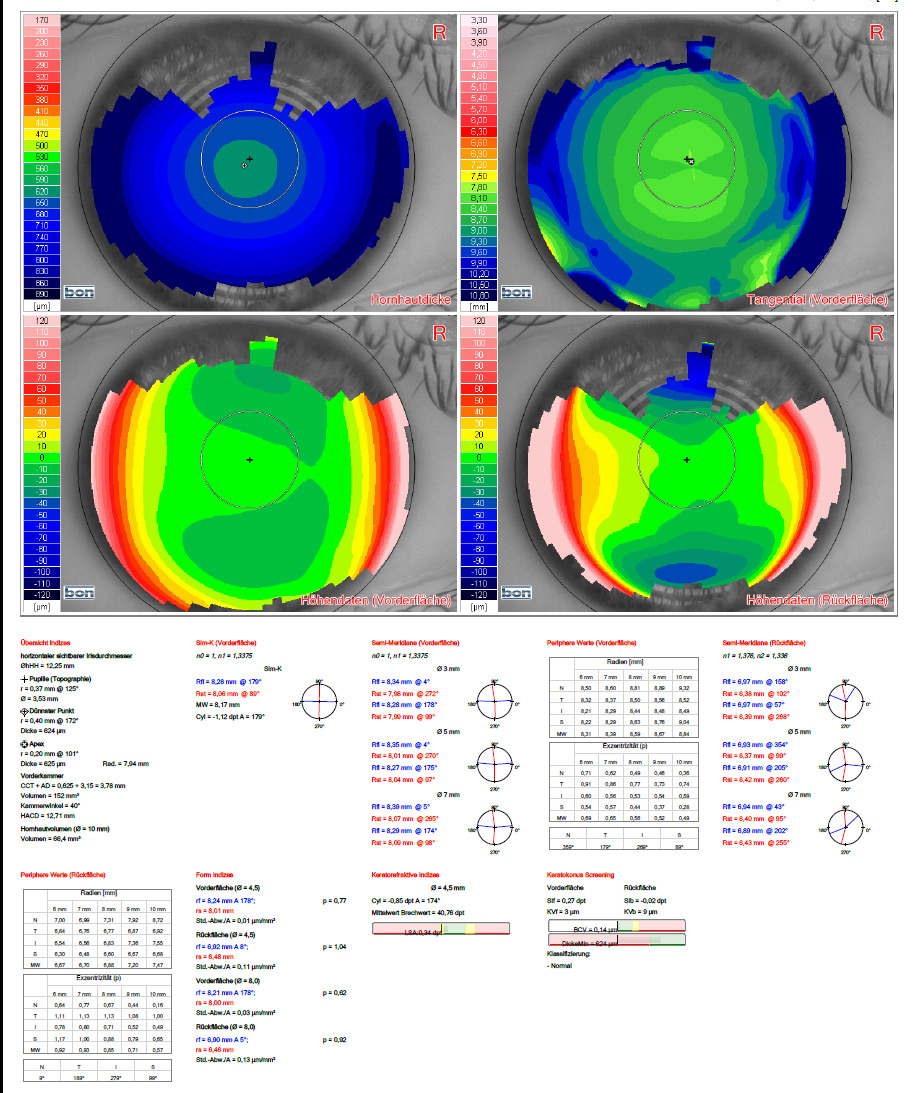

Darstellung des Hornhautreliefs bei starker Hornhautverkrümmung: es besteht der Verdacht auf einen Keratokonus (krankhafte Hornhautverkrümmung und -verdünnung).

Detaillierte Diagnostik zur Auswahl der passenden Linse vor der Operation des Grauen Stars.

Hornhauttopographie

Die genaue Erfassung und Darstellung der Hornhaut ermöglicht eine Reihe von Erkenntnissen. Das Wissen um die genaue Beschaffenheit der Hornhaut hilft z.B. bei der Anpassung von Kontaktlinsen wie auch bei der Diagnostik von Hornhauterkrankungen wie Keratokonus.

Die Analyse der Hornhaut mittels einer hochauflösenden Topographie ist darüber hinaus auch vor der Durchführung refraktivchirurgischer Eingriffe, z.B. LASIK oder der Implantation von Multifokallinsen bei der Operation des Grauen Stars erforderlich.